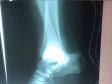

18.09 был перелом наружной лодыжки правой голени, вывих правой большеберцовой кости, оскольчатый перелом с/з малоберцовой кости со смещением к/отломков. 24.09 травматолог доделала гипс, но с того времени отёк спал ещё больше. Сейчас гипс болтается, не спадает, конечно, но почти вся ладонь может пролезть внутрь. Вертикально ногу держать очень больно, только горизонтально. Стоит ли обратиться к травматологу для коррекции гипса? Или так и должно быть? Следующий плановый визит только 10.10.